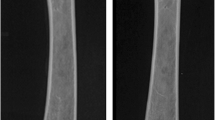

Prior to the mechanical testing, the ankle and knee were disarticulated and all soft tissues were removed, leaving the tibio-fibular complex. This was embedded in Permatex resin (Fig. 2) (Permatec inc, Hertford, Connecticut, USA) in a mounting block, then placed in an Instron mechanical testing machine (Instron Corporation, Massachusetts USA) and loaded in compression to failure at a rate of 2 mm/min using a 10-kN load cell.

This measured displacement (mm) for increasing load (Newtons) until failure, and the data were saved as an Excel spreadsheet and exported to Easy Plot (Spiral Software Norwich, Vermont USA) and produced load displacement curves for each specimen.

The length of exposed bone (lo) was measured prior to compression testing (Fig. 2). The mean area of the regenerate was calculated from DXA measurements and the load/displacement data were transformed to produce a stress/strain graph from which range, mean and standard deviation were calculated for the following parameters (Table 1):